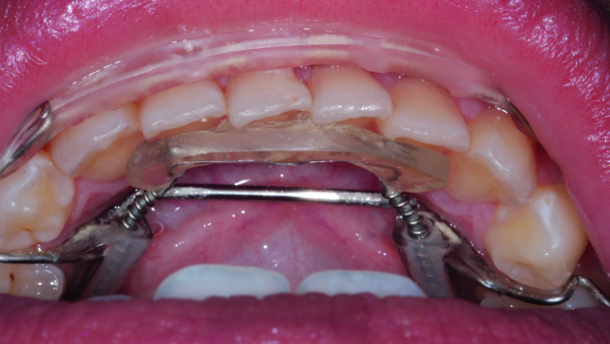

The Inman Aligner is a simple removable appliance, a modification of the removable spring retainer. It uses super-elastic coil springs to apply highly efficient light and consistent forces on both the labial and lingual surfaces of the anterior teeth (Figs. 1 & 2). The appliance is fabricated on a cast on which, based on a surgical model, the anterior teeth needing correction have been removed and reset in the ideal position in wax on the working cast.[3] When the patient wears the appliance, the built-in forces generated by the spring coils will correct the misaligned anterior teeth (Fig. 3).

The patient presented in this case was bothered by the look of his overlapping maxillary central incisors (Figs. 20 & 21). His mandibular teeth were also crowded, but for some reason, his concern was only with his maxillary teeth. He had started to hide his smile in front of his friends, feeling embarrassed to show his maxillary teeth. After the full orthodontic examination and discussion about all of the treatment options, including comprehensive orthodontic treatment, the patient chose the removable Inman Aligner system owing to its flexibility in that the wearer is able to remove the appliance for several hours a day and because of its short treatment time. The maxillary left central incisor would have been aggressively prepared had it been treated restora tively.[7–9] By using a simple anterior alignment tech nique, the treatment took only eight weeks to straighten the teeth and a great deal of sound enamel tissue was preserved by conservatively resolving the unattractive appearance of the maxillary teeth (Figs. 22 & 23).